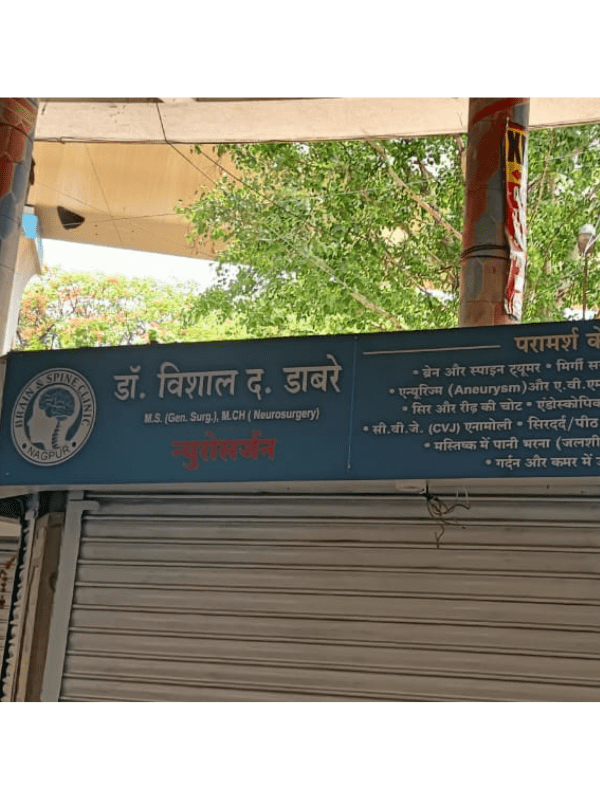

Dr. Vishal Dabare

Best Neurosurgeon in Nagpur | MBBS, MS GENERAL SURGERY- , MCH - NEUROSURGERY.